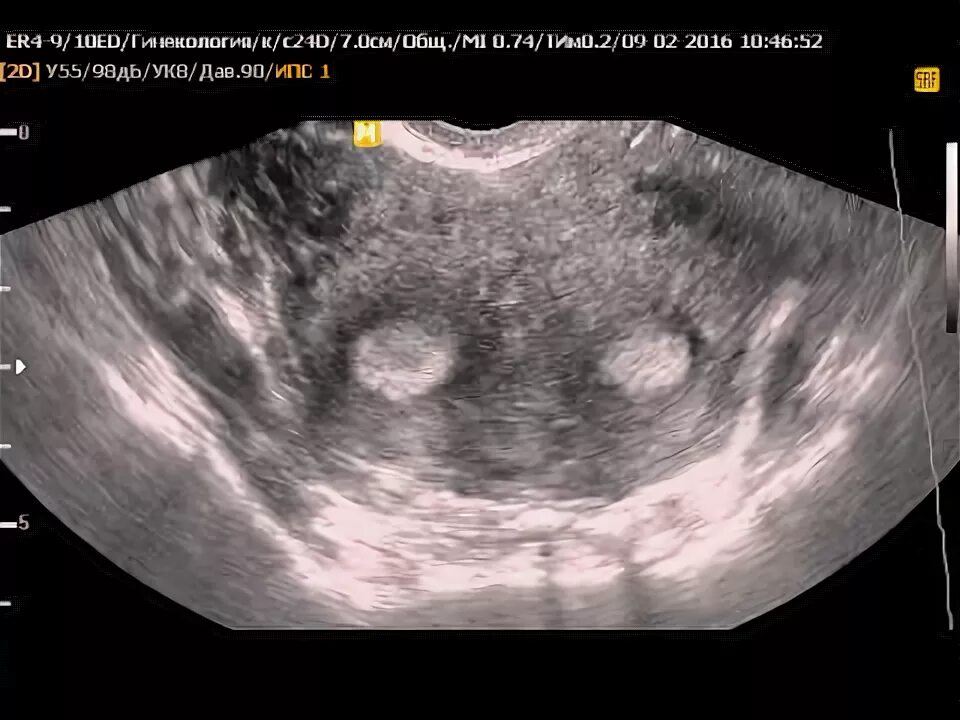

Может ли быть у девушки 2 матки